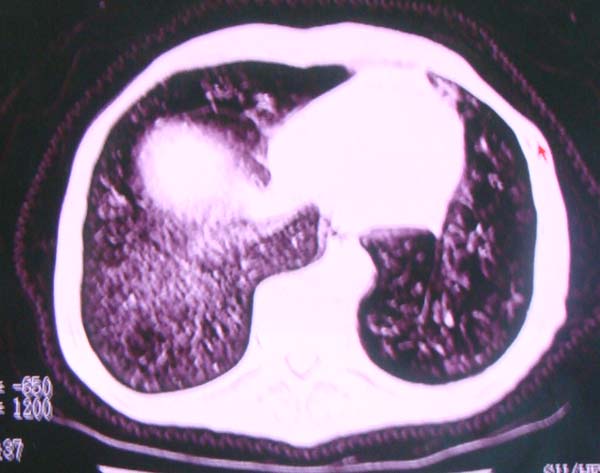

以下是引用zhangzhongshou在2008-2-15 22:25:00的发言:[br]片子照得不清,基本考虑1、细支气管肺泡癌2、亚急性血行播散型肺结核。请结合临床。片子细节显示不清,无法提供进一步意见。

以下是引用杀毒软件在2008-2-15 22:34:00的发言:[br]小叶中心性肺气肿。两肺弥漫性病变,肺泡微石病,过敏性肺炎,尘肺2期,特发性肺纤维化都有可能。[br]不象肺泡癌。